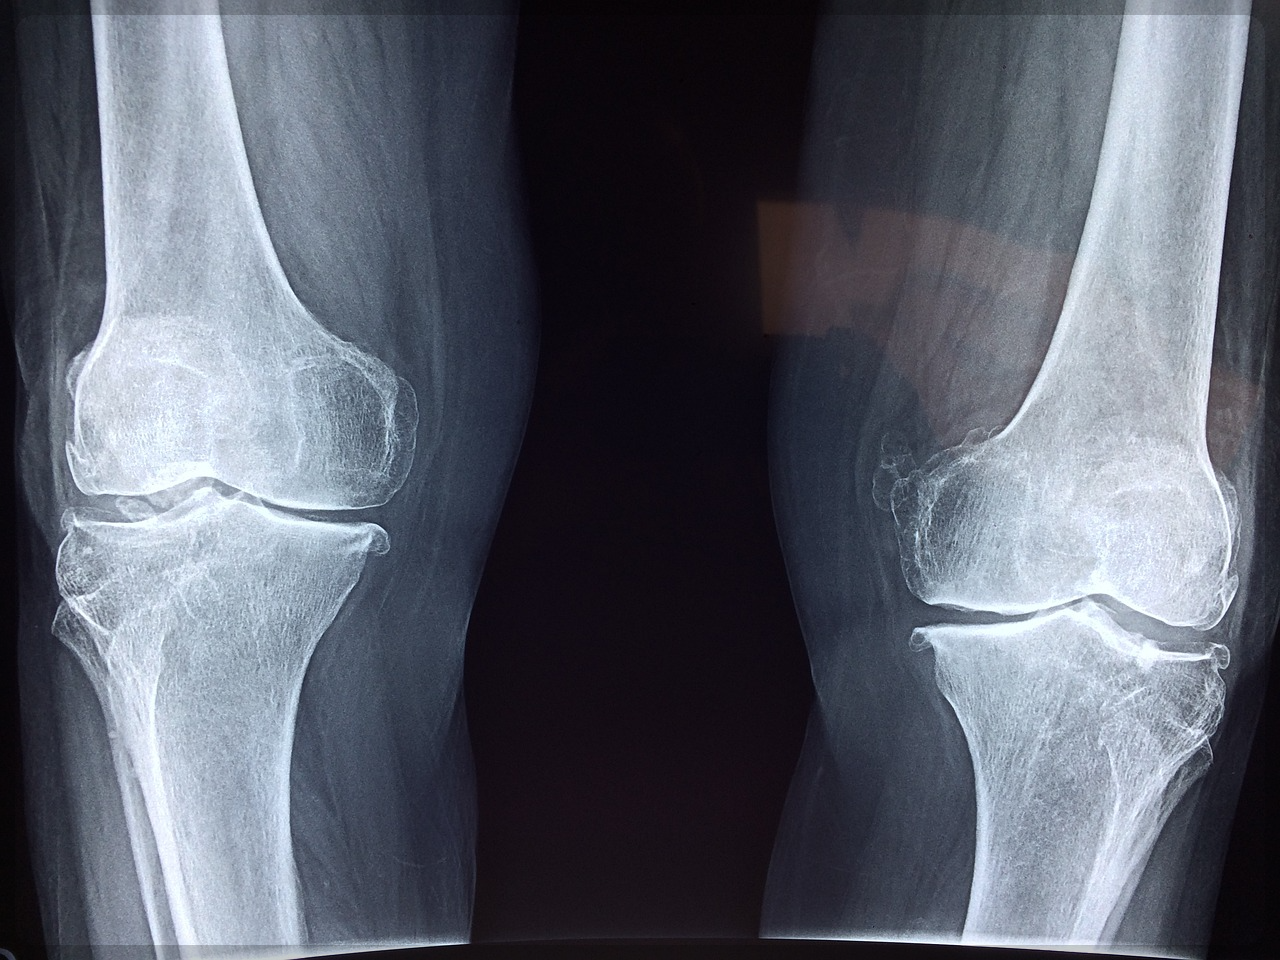

그런데 안심할 수는 없습니다. 왜냐 관절 연골에는 조직 재생을 돕는 혈관과 신경이 없어서 연골이 닳아도

통증을 느낄 수 없다고 하는데요.

즉 연골에는 통증을 느끼는 신경이 없어서 관절에 염증이 생기고 나서야 통증을 느낀다는 겁니다.

이렇게 통증을 느낀다면 이미 염증이 발생한 이후이기 때문에 관절염 조기 치료가 어렵다는 거죠.

또한 골관절의 경우 손상이 되면 손상으로 인한 염증 반응과 이를 보상하기 위한 연골 재생 반응이 동시에

일어난다고 해요.

즉 염증 반응, 재생 반응 두 가지가 동시에 일어나는데 이때 관절의 재생 속도가 손상 속도를 따라잡지 못하면서

관절 연골의 손상이 점점 더 심화된다는 겁니다.

이처럼 연골은 소모성 기관으로서 재생되지 못한다는 특징이 있는데요.